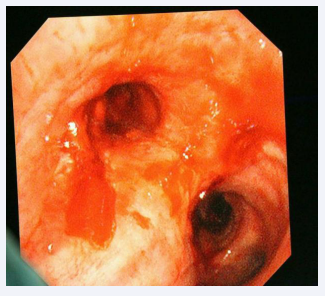

Bronchoscopic examination revealed significant thickening of the right middle and lower lobar bronchus, marked stenosis of the bronchial origin of the right middle lobe. Additionally, the opening of the bronchus in the lower lobe of the right lung remained open, and necrotic granulation tissue was visible, including a large cavity with obvious necrotic lung tissue surrounded by brown necrotic materials (Figure 2).

Bronchoscopy findings.

Figure 2: Bronchoscopy findings.